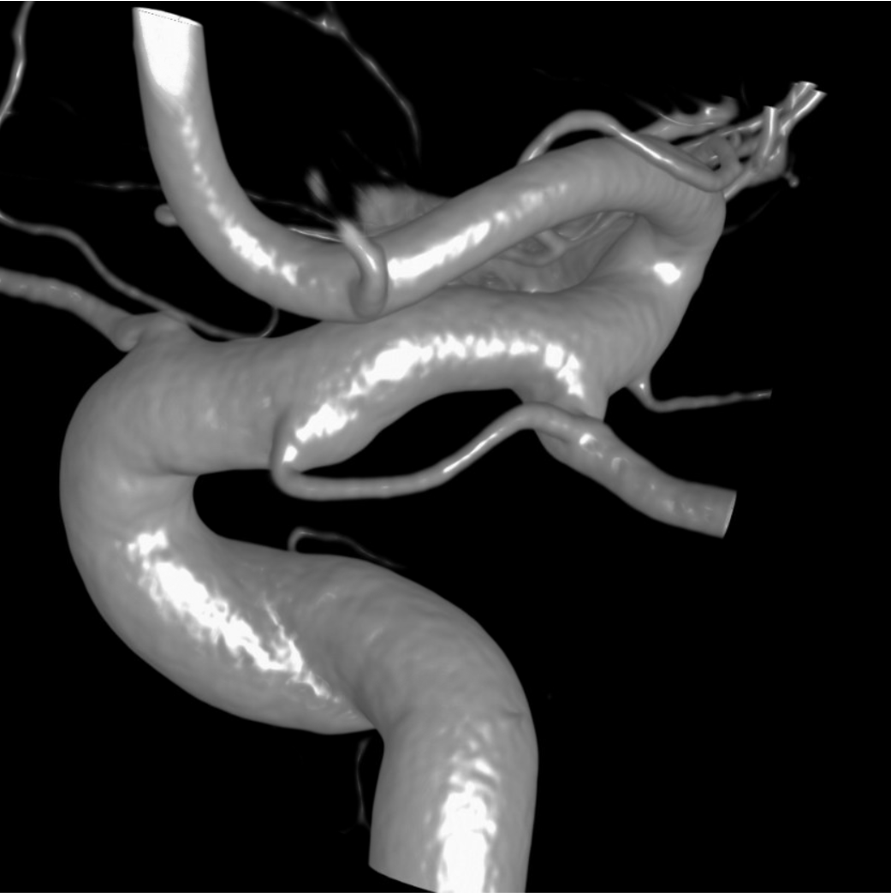

Below is a Volume Rendered typical arrangement — a slender (but still large by its own standards) superior hypophyseal supplies the stalk (and anterior pituitary), while inferior hypophyseal from MHT supply the posterior pituitary.

Sagittal MIP of the pituitary